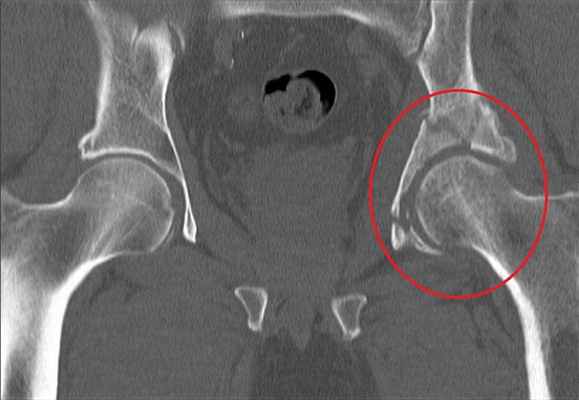

Для уточнения диагноза выполняют обзорную рентгенографию таза и рентгенографию поврежденного сустава в трех дополнительных проекциях. По возможности пациента направляют на КТ таза, поскольку эта методика позволяет более точно оценить тяжесть травмы и характер смещения отломков. Диагностическая ценность компьютерной томографии возрастает при повреждениях задней колонны и оскольчатых переломах.

При подозрении на перелом вертлужной впадины помимо стандартной рентгенограммы таза в прямой проекции ( AP ) с захватом тазобедренных суставов выполняли косую подвздошную и косую запирательную проекции по Judet [12]. Для детализации повреждений осуществляли компьютерную томографию таза с 3D-реконструкцией, это являлось важным условием для выбора тактики лечения, операционного доступа и метода фиксации.

При поступлении пациента с травмой вертлужной впадины наличие у него вывиха в тазобедренном суставе являлось показанием к его экстренному вправлению с последующим наложением скелетного вытяжения или аппаратной фиксацией. Это является залогом успеха последующей реконструкции. Так, на рисунке 1 слева представлена рентгенограмма пациента с переломом задней колонны левой вертлужной впадины со смещением и вывихом бедра. Вправление вывиха бедра в экстренном порядке привело к репозиции перелома задней колонны вертлужной впадины (рис. 1 справа), что в дальнейшем облегчило выполнение остеосинтеза.

Рисунок 1. Рентгенограммы мужчины 32 лет. Автодорожная травма (удар в область левого колена при столкновении): слева – при поступлении, перелом задней колонны левой вертлужной впадины со смещением, вывих левого бедра; стрелка указывает на смещение фрагмента задней колонны; справа – после вправления вывиха в экстренном порядке наступила репозиция перелома; стрелка указывает отсутствие смещения